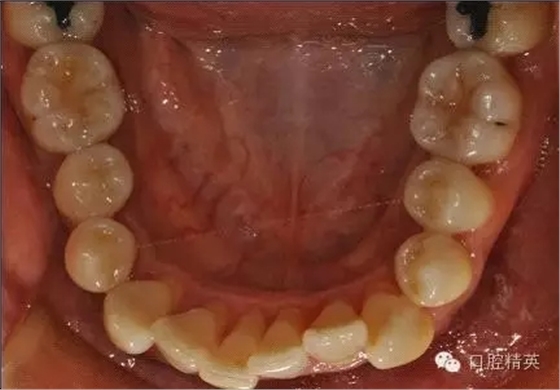

本病例 :女 34歲,主訴刷牙出血,覺(jué)牙齒輕度松動(dòng)一年。

檢查見(jiàn)大量齦上及齦下結(jié)石,探診出血,牙周袋較深,32-42 II度松動(dòng)。X線片顯示牙槽骨水平吸收。

診斷:成人慢性廣泛性中度牙周炎。

治療計(jì)劃:口腔衛(wèi)生宣教,刷牙指導(dǎo),齦上潔治,齦下刮治術(shù),下頜牙33-43牙周固定。

治療前: